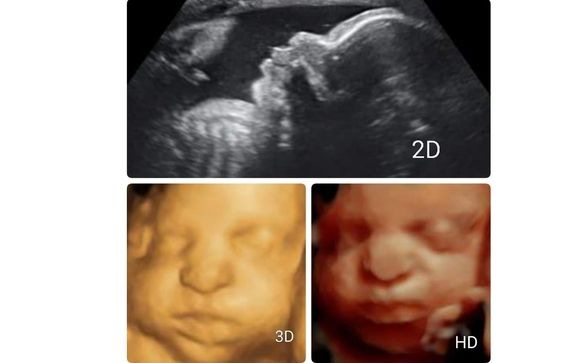

A Little Insight 3d 4d 5d Ultrasound 213 Photos 178 Reviews

33 Weeks So Cute A Little Insight 3d 4d 5d Ultrasound Facebook